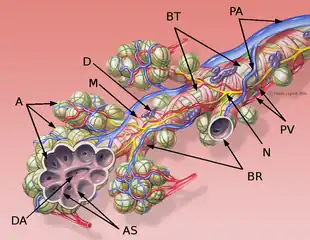

Alveoli are first located in the respiratory bronchioles that mark the beginning of the respiratory zone. They are located sparsely in these bronchioles, line the walls of the alveolar ducts, and are more numerous in the blind-ended alveolar sacs.[5] The acini are the basic units of respiration, with gas exchange taking place in all the alveoli present.[6] The alveolar membrane is the gas exchange surface, surrounded by a network of capillaries. Oxygen is diffused across the membrane into the capillaries and carbon dioxide is released from the capillaries into the alveoli to be breathed out.[7][8]

The alveoli are first located in the respiratory bronchioles as scattered outpockets, extending from their lumens. The respiratory bronchioles run for considerable lengths and become increasingly alveolated with side branches of alveolar ducts that become deeply lined with alveoli. The ducts number between two and eleven from each bronchiole.[10] Each duct opens into five or six alveolar sacs into which clusters of alveoli open.

Each terminal respiratory unit is called an acinus and consists of the respiratory bronchioles, alveolar ducts, alveolar sacs, and alveoli. New alveoli continue to form until the age of eight years.[5]

Blood circulation around alveoli_(14577681128).jpg.webp) Diagrammatic view of lung showing magnified inner structures including alveolar sacs at 10) and lobules at 9).

Diagrammatic view of lung showing magnified inner structures including alveolar sacs at 10) and lobules at 9).